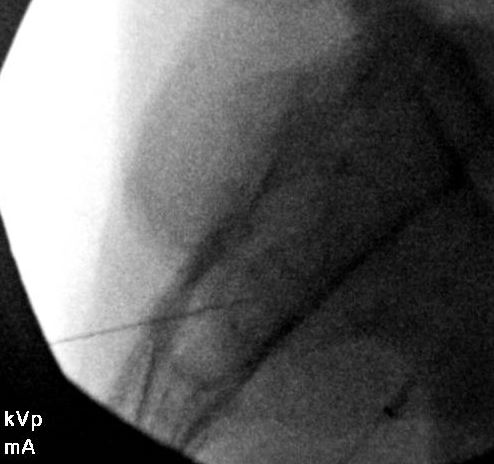

I don't ever take laterals unless things really aren't adding up or I've got a medical student and I'm trying to be academic. Here are a few below.

Typically start 5-10 degrees feet tilt, 10-15 degrees contra-oblique and then adjust the oblique until I find what seems right for the joint.